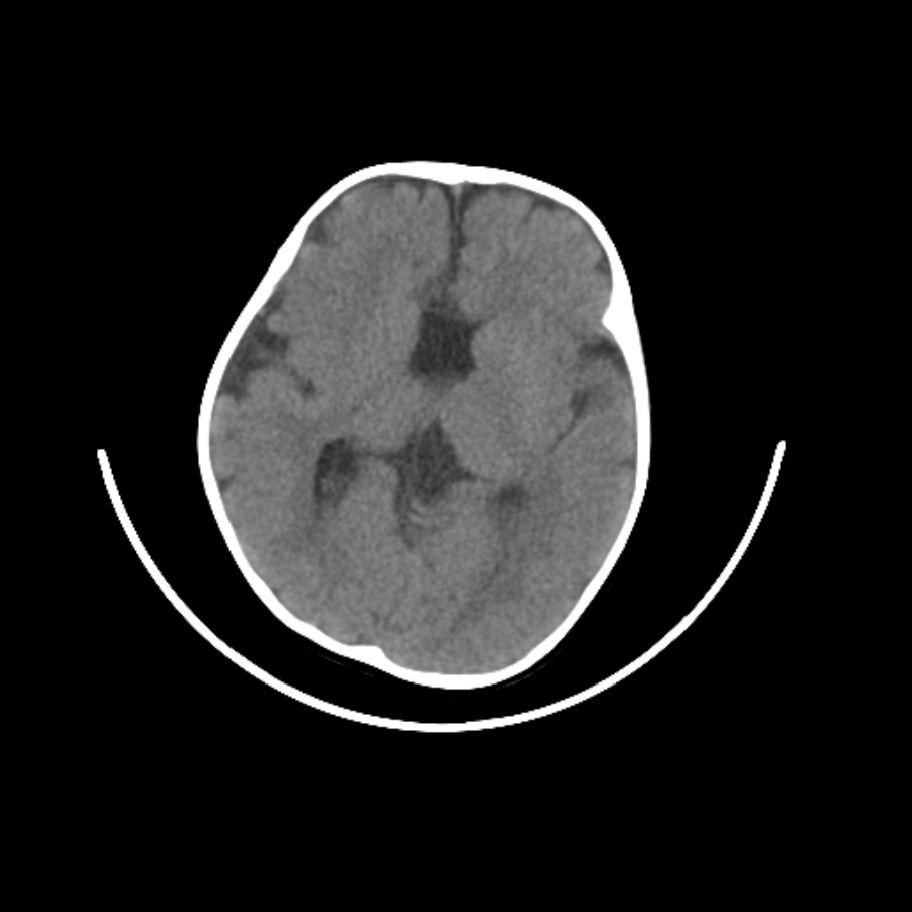

以下是引用随光逐影在2009-4-8 7:51:00的发言:[br]1)透明隔缺如(视-隔发育不良?)。2)右侧脑裂畸形。3)右侧幕上半球脑萎缩。